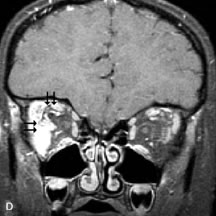

PATIENT PREPARATION Before MRI is performed, patients must be screened and prepared to avoid the potential hazards associated with the strong magnetic field. Patients who have ferrous aneurysm clips or cardiac pacemakers, who depend on life-support equipment, or who retain a possible metallic intraocular foreign body are not candidates for this imaging modality. MRI cannot be performed on obese patients who cannot fit into the bore of the magnet. Patients who are claustrophobic may not tolerate a prolonged period of study within the confines of the magnet, whereas others might do well if given a mild sedative. All worn metallic objects (e.g., necklaces, watches) should be taken off, credit cards set aside, and eye makeup removed before entering the room containing the magnet.5,20,34,35,36 NORMAL ORBITAL ANATOMY T1-weighted images provide the best anatomic details of the orbit because they display superior contrast resolution between normal structures (see Fig. 8). The vitreous has a long T1, resulting in an intermediate signal similar to brain, whereas the crystalline lens and sclera appear dark because of a longer T1 and short T2. The extraocular muscles, like all skeletal muscles, demonstrate a moderately long T1 and short T2 and highly contrast with the intense signal of the surrounding orbital fat (adipose tissue has an extremely short T1). The lacrimal glands appear as mottled areas of reduced intensity of the signal from the orbital fat in the lacrimal fossa. The optic nerves are seen with the same signal intensity as brain white matter and are hypointense relative to the orbital fat because their Tl is longer than the Tl of fat but shorter than the Tl of water. Cortical bone is not well delineated because it contains little free water, yielding minimal signal in MRI, and thus appears dark on all pulse sequences. This feature explains why MR images of the orbital apex and intracanalicular portion of the optic nerves are superior to comparable CT scans. Partial volume averaging of the bones in these regions obscures soft tissue details on CT images, whereas MRI reveals the signals only from the soft tissue structures with no cortical bone input. Bone marrow, on the other hand, is seen as a relatively intense signal because of its high fat content (see Fig. 8).37,38 T2-weighted pulse sequences are not ideal for imaging normal anatomy; however, they are particularly useful in revealing pathologic conditions (see Fig. 9). T2-weighted studies are most easily recognized by a bright vitreous signal. ORBITAL DISEASES Vascular Lesions Cavernous hemangiomas appear as well-circumscribed, smooth, usually intraconal masses that are isointense to muscle on T1-weighted images and hyperintense on T2-weighted images (Fig. 12). Patchy early enhancement is typically followed by diffuse, more homogeneous enhancement.39 The internal architecture of the mass, including septation and internal vasculature, may often be appreciated with high-quality orbital imaging.40 Lymphangiomas consist of ectatic vascular channels within a connective tissue stoma with varying degrees of lymphoid cellularity. On MRI, these tumors are typically poorly circumscribed, multicompartmental, and heterogeneous, often showing cystic dilations with fluid levels (Fig. 13). The signal characteristics within lymphangiomas vary considerably, reflecting cystic and solid components and the varying paramagnetic characteristics of blood at different stages of degradation.40–42 Acute hemorrhage appears hypointense on both T1- and T2-weighted formats. Methemoglobin present in subacute hemorrhage (3 to 14 days) leads to hyperintense signal on both T1- and T2-weighted images.41 A small percentage of lymphangiomas appear radiologically indistinct from orbital cavernous hemangiomas.43 Orbital varices are venous malformations that expand with increased systemic venous pressure, such as with Valsalva maneuvers. Because rapid acquisition of images during a Valsalva maneuver is important in imaging such a lesion, conventional or spiral CT is currently the modality of choice.44 MRI is an excellent modality for demonstrating enlargement of the cavernous sinus and dilation of the superior ophthalmic vein in patients with high-flow carotid-cavernous fistulas (Fig. 14).37MRA may be helpful in the evaluation of the venous outflow pattern. The rapidly flowing blood in these vascular structures carries the excited protons out of the section before they can be imaged, resulting in their dark appearance.5 In low-flow dural arteriovenous malformations, MRA may help define the arterial feeding vessels.45 Neural Lesions MRI is more effective than CT in delineating the intracranial optic nerves, chiasm, and optic tracts and, for this reason, is the preferred imaging modality in the evaluation of optic nerve disorders. The spatial relationships and image contrast of the orbital tissues with intraorbital optic nerve tumors is comparable between the two imaging modalities. The normal nerve is isointense to brain and appears enlarged and kinked owing to infiltration of an optic nerve glioma on T1-weighted images. Gliomas appear hyperintense on T2-weighted images and may be heterogeneous owing to cystic areas within the tumor. Contrast enhancement is variable.46 Intraorbital and intracranial optic nerve sheath meningiomas are usually isointense to cortical gray matter on Tl-weighted images and remain isointense on proton density studies (Fig. 15). Gd-DTPA is useful in delineating the intracranial extension of optic nerve meningiomas.7,47 The hyperostosis of bone and calcification associated with meningiomas are not demonstrated as well on MRI studies as on CT scans.20,37 Gd-DTPA–enhanced MRI also appears promising in the study of the permeability of the blood–brain barrier in selected optic neuropathies.22,48 MRI may reveal an enlarged optic nerve and some degree of contrast enhancement in cases of optic neuritis.49 Muscle Disorders Extraocular muscle enlargement in patients with thyroid-associated orbitopathy is demonstrated equally well with CT and MRI studies. However, the superior tissue contrast on MR images reveals better details of the relationships of the optic nerve to the thickened muscles at the orbital apex (Fig. 16).50 In addition, MRI may be able to differentiate between muscles that are enlarged as a result of edema and active inflammation and those enlarged because of fibrosis by their T2 relaxation times.21 Quantitative MRI was not found to be accurate in predicting the success of low-dose orbital irradiation.51 However, a muscular index relating the diameters of the rectus muscles to the bony orbital dimensions was useful in predicting optic nerve compression.52 MRI is also effective in imaging orbital tumors of mesenchymal origin, such as rhabdomyosarcoma, particularly in the assessment of extension into the anterior and middle cranial fossae (Fig. 17).37 The lack of any pathognomonic radiologic features necessitates rapid orbital biopsy when rhabdomyosarcoma is suspected. Osseous Lesions In general, CT is the imaging modality of choice when details of quantity and quality of bone are needed; however, abnormalities of bones can be detected indirectly by MRI. Cortical bone appears black (signal void) on MR images because of its low proton density and free-water content. The absence or discontinuity of the signal void of the orbital walls may represent bony destruction or fracture. Hyperostosis associated with prostate metastases or meningioma is visualized as areas of black smudging.50,53 Diseases in which the bone is replaced by pathologic tissues with a high free-water content, such as fibrous dysplasia, are well demonstrated on MRI. An intermediate signal intensity on T1-weighted images and hypointense signal on T2-weighted images is representative of fibrous dysplasia. Enhancement on post–Gd-DTPA MR scans is seen and is more evident in areas that are less mineralized.54 Cystic Lesions Dermoid cysts appear as rounded, well-defined lesions typically contiguous with an orbital bony suture. The high-intensity signal on T1-weighted images is attributed to the sebaceous-produced lipid contents (Fig. 18).31,50 Mucoceles may demonstrate a hypointense or hyperintense signal on MR images, depending on the concentration of proteinaceous or inflammatory fluid components. The integrity of the bony walls of the expanded sinus cavities cannot be assessed on MR as well as by CT.37,50,55,56 A high-signal intensity on Tl- and T2-weighted images is characteristic of orbital chronic hematic cysts because of the blood-breakdown products within the cysts.57 Trauma Although soft tissue relationships are usually better demonstrated on MRI, the evaluation of craniofacial bony trauma is preferable with CT. For example, prolapse of orbital fat through a fracture site and hemorrhage of adjacent tissues are demonstrated in an MR image, but the actual fractured bone is not imaged. Three-dimensional MRI of the orbit in subacute trauma has been described,58 although its precise role is not currently established. MRI has been suggested to be superior to CT in detecting intraorbital wooden foreign bodies.59,60 In a series of penetrating orbital injuries with organic foreign bodies, however, MRI was able to identify the foreign body in only four of seven cases.61 With an in vitro model for wood foreign body, McGuckin and colleagues concluded that CT was the imaging modality of choice.62 A careful history and, in selected cases, plain films to rule out a metallic foreign body are crucial before MRI is considered in patients with periocular trauma. MRI is particularly helpful in the detection and characterization of subperiosteal hematomas of the orbit (Fig. 19). They are most commonly seen in the subperiosteal space of the superior orbit as well-defined masses following a traumatic injury. The signal intensity varies depending on the acute, subacute, or chronic nature of the hematoma, based on the stage of blood degradation. Fresh hemorrhages are hypointense on T1-weighted images and hyperintense on T2 images. Hematomas that are 1 to 7 days old are hypointense on both T1- and T2-weighted images. T1-weighted images of hematomas more than a week old are hyperintense due to the oxidation of deoxyhemoglobin to methemoglobin, whereas the T2 images remain hypointense.63 Metastatic Tumors Breast carcinoma metastatic to the orbit has been demonstrated to be hypointense to the surrounding orbital fat on T1-weighted studies and hyperintense on T2-weighted images and has an affinity to the extraocular muscles (Fig. 20).50,64 The MRI characteristics of prostate carcinoma metastatic to the orbit have been described as involving the greater and lesser wing of the sphenoid, orbital roof, and optic canal. Diffuse bone hypertrophy with isointense or slightly hyperintense tissue on T1-weighted images represents the osteoblastic carcinomatous bone infiltration. Contrast enhancement is variable on T1-weighted and fat-suppressed images.65 Most other metastatic tumors also have a lower intensity signal on T1-weighted images and appear to displace or infiltrate normal orbital structures; however, their signal characteristics are variable on T2-weighted MR images.66 Many metastatic tumors demonstrate bright contrast enhancement with Gd-DTPA. Infectious Disorders MRI findings of preseptal and orbital cellulitis typically include increased signal intensities on T2-weighted images of the eyelids and orbital fat, respectively, due to the increased water content of the tissues. Since most cases of bacterial orbital cellulitis are associated with paranasal sinusitis, hyperintense signals of the affected sinuses may also be found on T2-weighted images as well as enhancement of polyps and granulation tissue on postgadolinium T1-weighted MR images. Subperiosteal abscess formation may occur due to contiguous spread of infection from the paranasal sinuses and appear on MRI as an area of intermediate signal on T1-weighted and proton-weighted MR images. The abscess may appear slightly hyperintense compared with muscle on T2-weighted scans with the necrotic contents having the greatest intensity.67 MRI and MRV are more sensitive than CT in revealing cavernous sinus thrombosis. Engorgement of the cavernous sinus, extraocular muscles, and ophthalmic veins is seen with hyperintensity of the thrombosed sinuses evident on all pulse sequences. The enlarged, thrombosed superior ophthalmic vein appears less hypointense than the normal contralateral ophthalmic vein, and hyperintensity within the lumen of the vessel may be seen on T1- and T2-weighted MR images.68 Inflammatory and Lymphoproliferative Lesions Inflammatory conditions of the orbit, both idiopathic (inflammatory pseudotumor) and those of known causes, have been found to be hypointense to fat and isointense to muscle on Tl-weighted studies and isointense or slightly hyperintense to fat on T2-weighted images (Fig. 21).50,64,69 The more fibrous or sclerosing varieties have less signal intensity on T2-weighted images. Marked enhancement is seen in pseudotumor infiltrates after gadolinium administration.70 The same signal characteristics are demonstrated in patients with Tolosa-Hunt syndrome, with mass lesions seen in the cavernous sinuses and orbital apices.71 Lymphomas have MRI characteristics similar to those of inflammatory lesions in that they are hypointense to fat and isointense to muscle on T1-weighted images (Fig. 22). They may appear hyperintense to fat on T2-weighted images, perhaps owing to less fibrosis than that seen in orbital inflammatory pseudotumor, although this is not a consistent finding.31,50,66 Lymphoid tumors typically enhance moderately after contrast injection. Unfortunately, studies have shown that tumor density and homogeneity are similar between inflammatory and malignant orbital infiltrates, and MRI cannot differentiate these lesions.72,73 Lacrimal Gland Tumors Lacrimal gland lesions present special problems in diagnosis and management. Pleomorphic adenoma (benign mixed tumor) should not be biopsied, but rather excised in toto. On the other hand, for lymphoma and inflammatory infiltrates, incisional biopsy is more appropriate than complete excision of the lacrimal gland. Thus, preoperative clinical and radiologic evaluation are especially crucial in planning appropriate surgical management. Pleomorphic adenomas demonstrate long T1 and T2 signal characteristics. They may show heterogeneity on T2-weighted images74 and moderate to marked enhancement with contrast.75 Signal characteristics of adenoid cystic carcinoma include hypointensity to fat on T1-weighted images, hyperintensity to fat with increased T2 weighting, and isointensity to fat on proton density-weighted studies (Fig. 23).31,75 Secondary bony alterations of the lacrimal fossa associated with lacrimal gland tumors, such as remodeling (benign mixed tumor) or destruction (adenoid cystic carcinoma), are seen indirectly on MR images; however, bone windows on CT scans provide better delineation of these changes. In contrast to the round or globular appearance of benign or malignant epithelial tumors of the lacrimal gland, lymphoproliferative tumors usually appear to be molding or draping onto the globe and the surrounding bony orbit. LACRIMAL DRAINAGE SYSTEM DISORDERS MRI with surface coils provides excellent spatial resolution and tissue-specific signal intensities of the lacrimal drainage system. These parameters have been found useful to more accurately demonstrate the extent of lesions in the lacrimal sac and differentiate long-standing mucoceles from solid tumors than CT.76 Physiologic studies in patients with tearing disorders now include MR dacryocystography, in which Gd-DTPA is either placed topically in the conjunctival fornix or injected by cannulation into the lacrimal sac. They provide a detailed morphologic and functional analysis of the lacrimal excretory system; however, they are no more sensitive than digital-subtraction dacryocystography or CT dacryocystography.77–79 INTRAOCULAR TUMORS On MRI, uveal melanomas have a typical appearance that helps to differentiate them from other primary and secondary intraocular tumors as well as choroidal detachments. Pigmented melanomas are hyperintense on Tl-weighted images, hypointense on T2-weighted studies, and hyperintense on proton density–weighted examinations (Fig. 24).30,31,50,80–82 These signal characteristics have been attributed to the paramagnetic properties of melanin because of stable free radicals that shorten the T1 and T2 relaxation times. Moderate enhancement is seen on postgadolinium T2-weighted images. Gadolinium-enhanced T1-weighted images are particularly sensitive in detecting choroidal melanomas.83 MRI may be less sensitive in detecting extrascleral extension of tumor than echography performed by an experienced ultrasonographer.84 Tumors metastatic to the choroid are hyperintense on T1- and T2-weighted images.24 The signal characteristics, however, may be similar to those seen with choroidal melanoma. Choroidal hemangiomas, on the other hand, have an intermediate signal on T1-weighted sequences and become hyperintense on T2-weighted images50 as well as proton density–weighted images.81 Retinoblastomas display moderate signal intensity on T1-weighted studies and a low signal on T2-weighted images.31,80,85 Calcification can be easily detected by CT and ocular ultrasonography but is not imaged by MRI.25,50 The presence of optic nerve involvement is best evaluated by MRI. ACQUIRED ANOPHTHALMIA When an eye is removed owing to tumor or trauma, an implant is typically placed in the intraconal space. MRI may be useful in defining the size, shape, and position of such orbital implants.86 Porous hydroxyapatite or polyethylene implants are preferred by many surgeons performing enucleation or evisceration. A porous implant offers the possibility of supporting a motility coupling peg to increase the movement of the overlying prosthesis. MRI with contrast is used by some surgeons to evaluate the degree of fibrovascular ingrowth in hydroxyapatite87 and porous polyethylene88 implants prior to motility peg placement. |